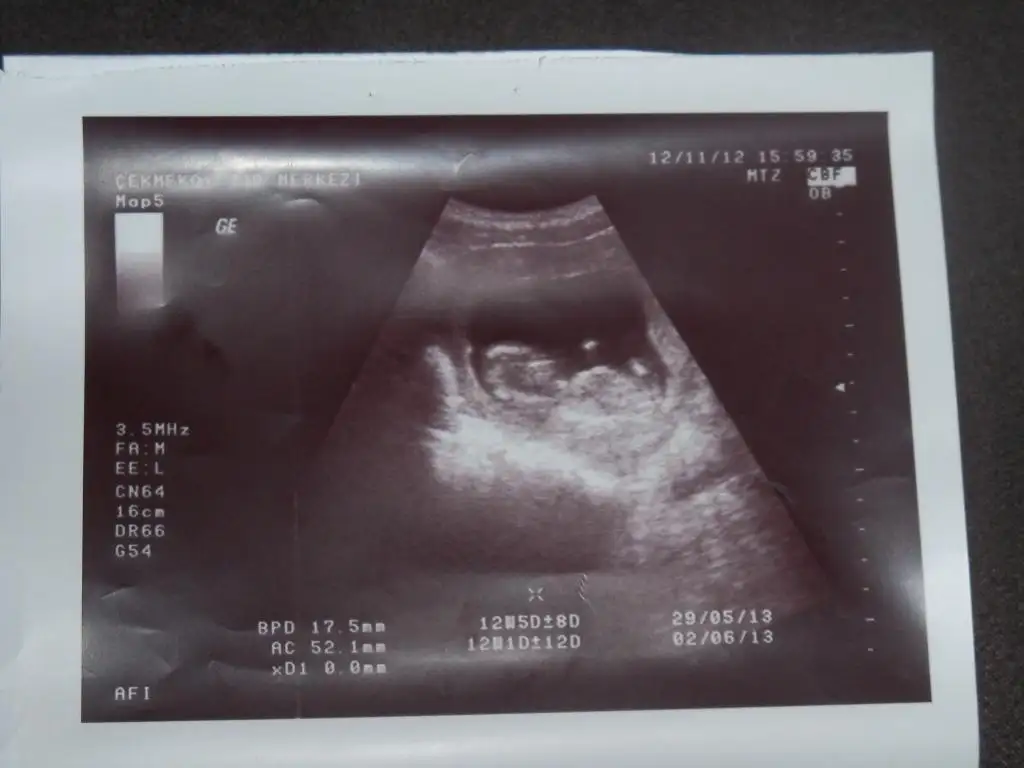

Eki Görüntüle 572552 Eki Görüntüle 572556 Eki Görüntüle 572559

bir tanesi 12+5 su en son ultrason goruntusunden ben hiç bişi anlamıyorum zaten neresi oldugunu

Solda kafasi var eli ve ayagi gozukuyor cnm nub yok su andaki resimde